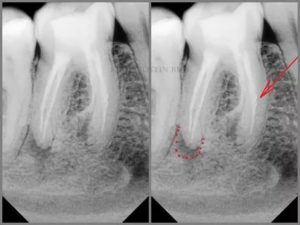

| Рис. 1 | На первом представленном R-снимке (рис. 1) видно, что удалось обойти обломок инструмента и все каналы зуба готовы к последующей пломбировке. На втором R-снимке (рис. 2) также виден обходной путь, канал запломбирован и обломанный инструмент включен в пломбировочную массу. | Рис. 2 |